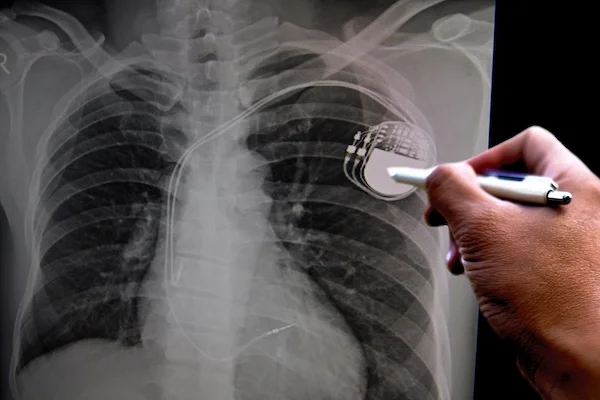

Zuverlässige Kontrolle für ein sicheres Herzgefühl.

Herzschrittmacher- und Defibrillator-Kontrollen

(aller gängigen Hersteller)

Regelmäßige Nachsorgeuntersuchungen sind entscheidend, um die einwandfreie Funktion von Herzschrittmachern und Defibrillatoren sicherzustellen. Dabei werden Batteriezustand, Elektrodenverbindungen und gespeicherte Ereignisse sorgfältig überprüft und die Einstellungen individuell angepasst. So kann eine optimale Funktionsweise des Geräts und damit Ihre Sicherheit gewährleistet werden.